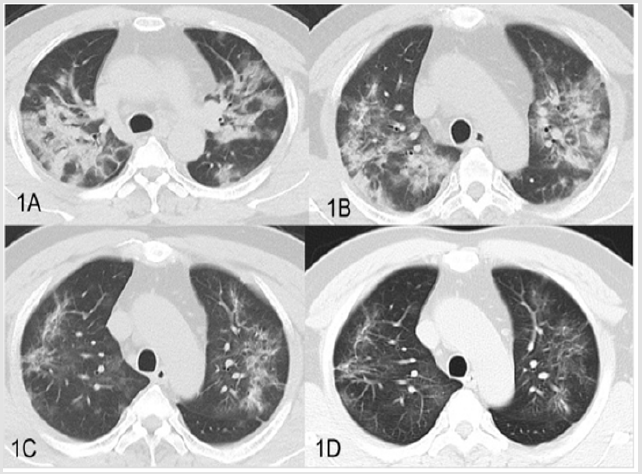

a. Case 1: Man, 40Y, was admitted to the hospital with fever and cough for 10 days. The patient’s wife (Case 2) developed fever on the way back from Wuhan. After admission, the new coronavirus nucleic acid tested positive. Multiple CT scans were performed (Figure 1) and the pulmonary lesions were significantly absorbed, thrice nucleic acid tests for new coronavirus infection were negative. The patient was released from isolation and discharged without fever and occasional cough.

Figure 1: CT images of cured group case1, 40-year old male. A. Patchy, ground hyaline lesions in both lungs, partial consolidation (2020/1/20). B. Bilateral lung plaques and ground glass gradually reduced absorption (2020/1/25). C. Double pulmonary disease with obvious absorption, progressive fibrosis (2020/2/1). D. Multiple ground glass slightly absorbed in both lungs, residual ground glass and fiber strips (2020/2/5).

In the cured group, the lung lesions in all patients showed a significant decrease in absorption, however,2 patients (2/3) were still with obvious ground glass or fiber strips (Figure1), but no consolidation were observed. 2 patients in isolation treatment group, multiple GGO, fibrosis and consolidation were observed (Figure 2). Our results showed that chest CT findings GGO and fibrosis had overlap in cured group and isolation group (Figure 2). Two cases in isolation group, the main CT findings were highly similar to that of cured patients.